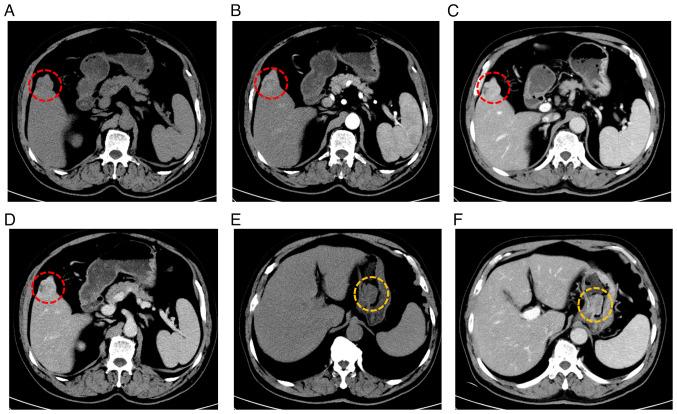

Primary gastric and liver cancers rank among the most prevalent malignant tumors of the digestive tract. Despite their serious implications for health, the global age-standardized incidence remains relatively low, at ~11.1 per 100,000 for primary gastric cancer and ~8.657 per 100,000 for primary liver cancer. Although the occurrence of multiple primary malignancies is not uncommon in clinical practice, reports of synchronous primary gastric and liver cancer are exceedingly rare. The present study describes a case involving a 60-year-old man diagnosed with synchronous primary gastric and liver cancer. The patient underwent endoscopic submucosal dissection for lesions located at the gastric angle, followed by laparoscopic resection of a small liver tumor. Pathological examinations revealed moderately differentiated intramucosal adenocarcinoma at the gastric angle and well-differentiated hepatocellular carcinoma in the liver. Following a 3-year follow-up, the patient remained in good health, with no evidence of disease recurrence. In conclusion, clinicians should exercise caution in patients presenting with distinct lesions to ensure that subtle malignancies are not overlooked, particularly in those with confirmed cancer. For patients with multiple cancers, it is crucial to ascertain whether the malignancies are primary, as this determination influences treatment strategies.

原发性胃癌和肝癌是消化道最常见的恶性肿瘤之一。尽管它们对健康有严重影响,但全球年龄标准化发病率仍然相对较低,原发性胃癌约为每10万人11.1例,原发性肝癌约为每10万人8.657例。虽然在临床实践中多重原发性恶性肿瘤并不罕见,但同步性原发性胃癌和肝癌的报道极为罕见。本研究描述了一例涉及一名60岁男性被诊断为同步性原发性胃癌和肝癌的病例。患者接受了胃角病变的内镜黏膜下剥离术,随后进行了小肝癌的腹腔镜切除术。病理检查显示胃角为中分化黏膜内腺癌,肝脏为高分化肝细胞癌。经过3年随访,患者健康状况良好,无疾病复发迹象。总之,临床医生对有明显病变的患者应谨慎,以确保不遗漏细微的恶性肿瘤,特别是在已确诊癌症的患者中。对于患有多种癌症的患者,确定恶性肿瘤是否为原发性至关重要,因为这一判定会影响治疗策略。